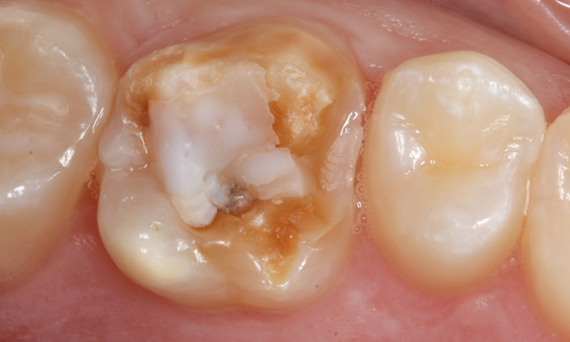

Before

First upper molar had been restored with an extensive yet insufficient composite filling that already showed visible fractures.

After

Chairside-fabricated restoration made from an advanced lithium disilicate ceramic, CEREC Tessera.